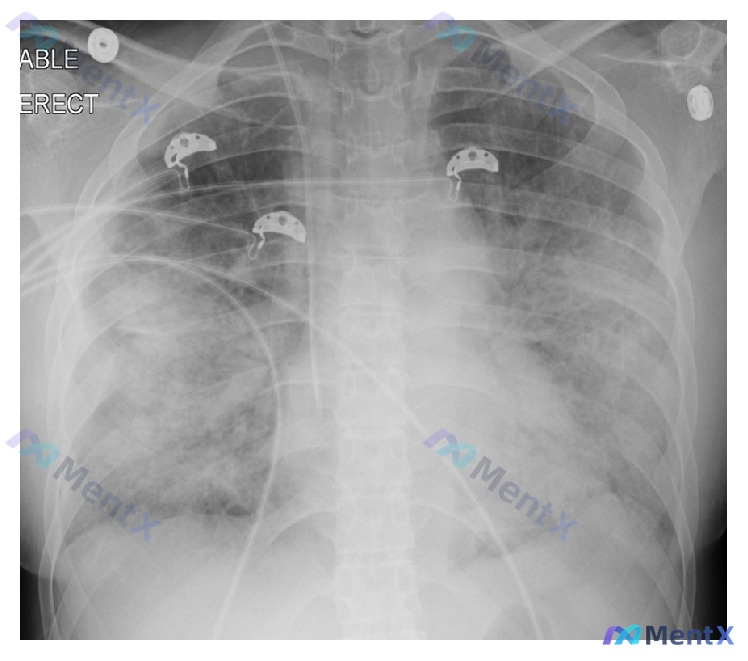

整理了一个挺有警示意义的病例,分享一下思路 看到一个病例资料:48岁女性,因肾盂肾炎和败血症住院,入院第二天突然出现急性严重呼吸困难,之前没有心肺疾病史。 先梳理下关键信息 基本生命征与体征 - 体温39.7°C,血压105/65mmHg,心率120次/分,呼吸36次/分 - 严重呼吸窘迫:鼻翼扇动...